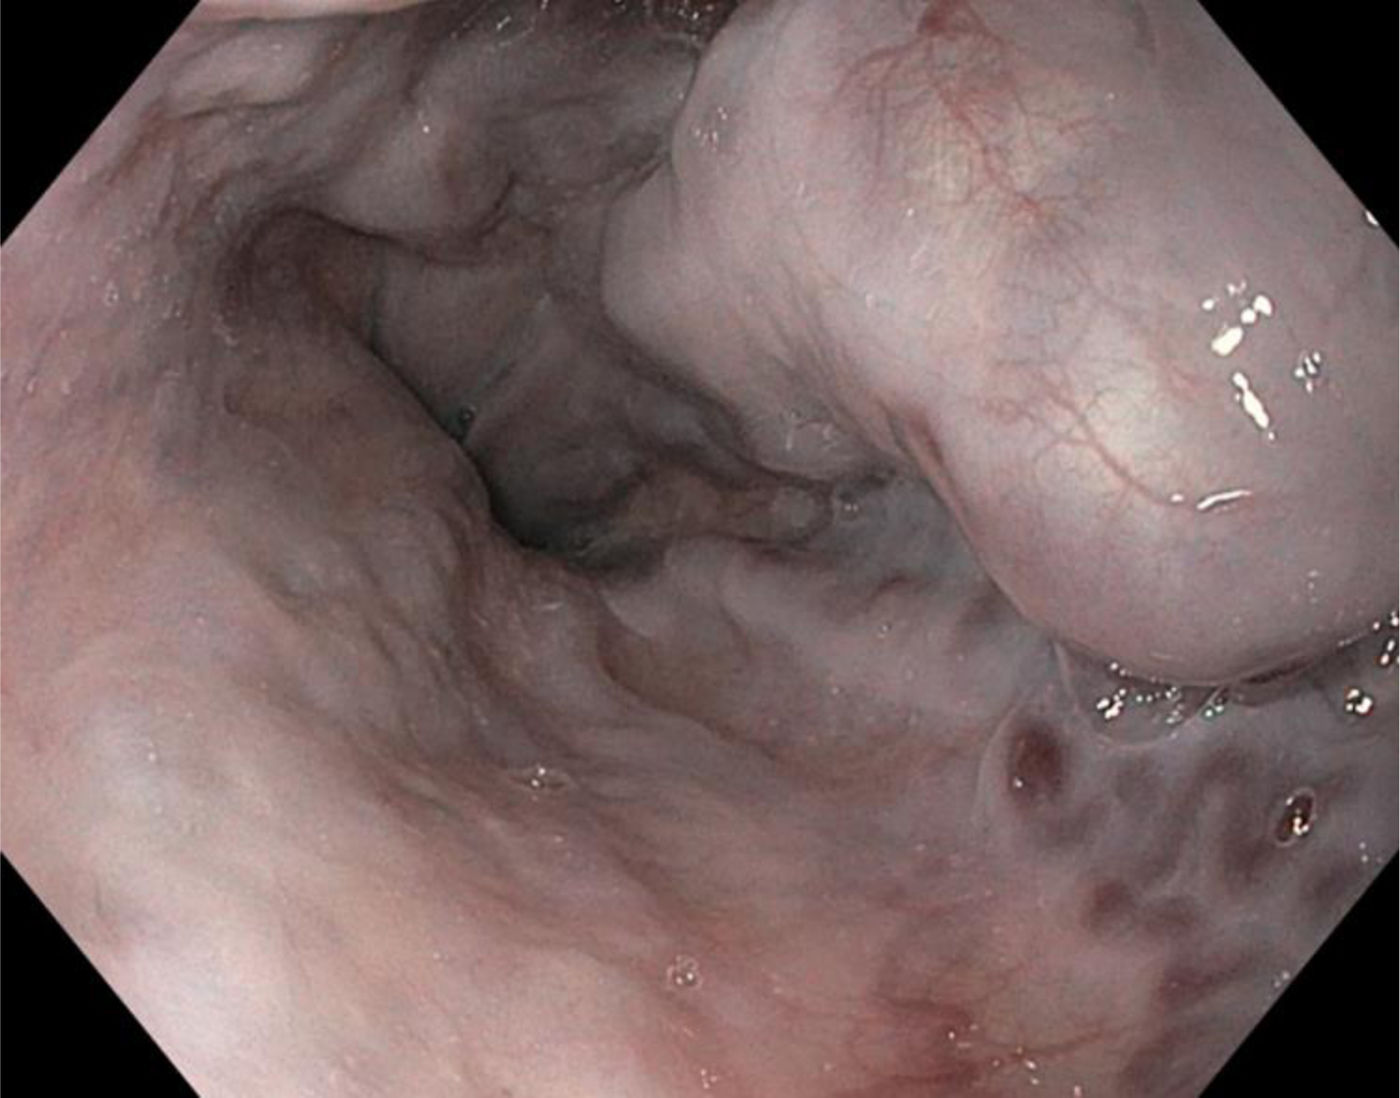

She was admitted to our hospital in June 2024 and programmed for EVL as an outpatient. In the gastroduodenal endoscopy (GDE), 3 large esophageal varices and one medium-sized varix were found. EVL was carried out using 3 elastic bands, with no immediate complications (Fig. 1). Ten days later, the patient arrived at the emergency service, presenting with hematemesis at a volume of 1000 cc, melena, and syncope.

GDE was performed, revealing an abundant amount of blood in the esophagus (Fig. 2A) arising from an actively bleeding post-ligation ulcer. The previously placed elastic band was becoming detached (Fig. 2B) and came completely detached during the procedure (Fig. 2C). In addition, 3 large varicose cords that were distally ligated were identified. A new ligation at the level of the post-ligation ulcer was unsuccessfully attempted. With the aid of an endoscopic cup, a hemostatic clip was placed, achieving complete hemostasis (Fig. 2D).